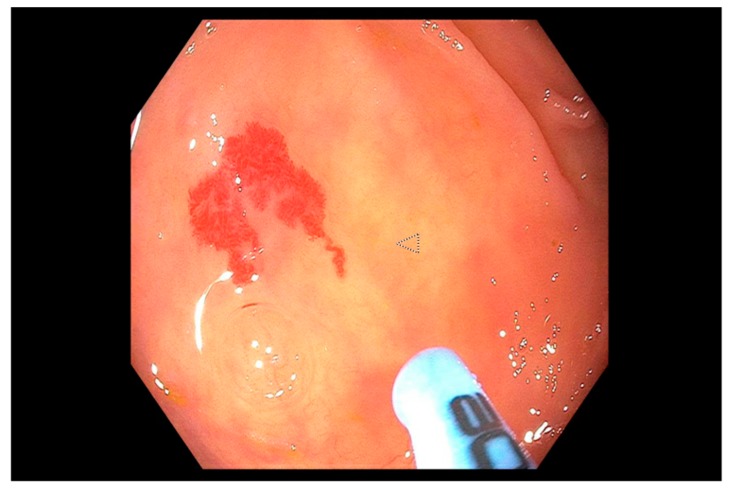

Endoscopic therapy is indicated for the treatment of ulcers with stigmata of recent hemorrhage (SRH) that carry a higher risk for recurrent bleeding and mortality [18,66]. These stigmata as described by the Forrest classification [79] in descending order of risk of rebleeding are: Class Ia, spurting hemorrhage (90%); Class IIa, nonbleeding visible vessel (50%) (Figure 1), Class Ib, oozing hemorrhage (10–20%); Class IIb, adherent clot (25–30%) (Figure 2); Class IIc, flat pigmented spot (7–10%) and; Class III, clean ulcer base (3–5%). Most patients with ulcer bleeding have low risk Forrest IIc and Forrest III lesions [45], and endoscopic treatment is not recommended [18,66].

Figure 2.

Gastric ulcer with an adherent clot (Forrest IIb ulcer) with active oozing seen in the gastric body.